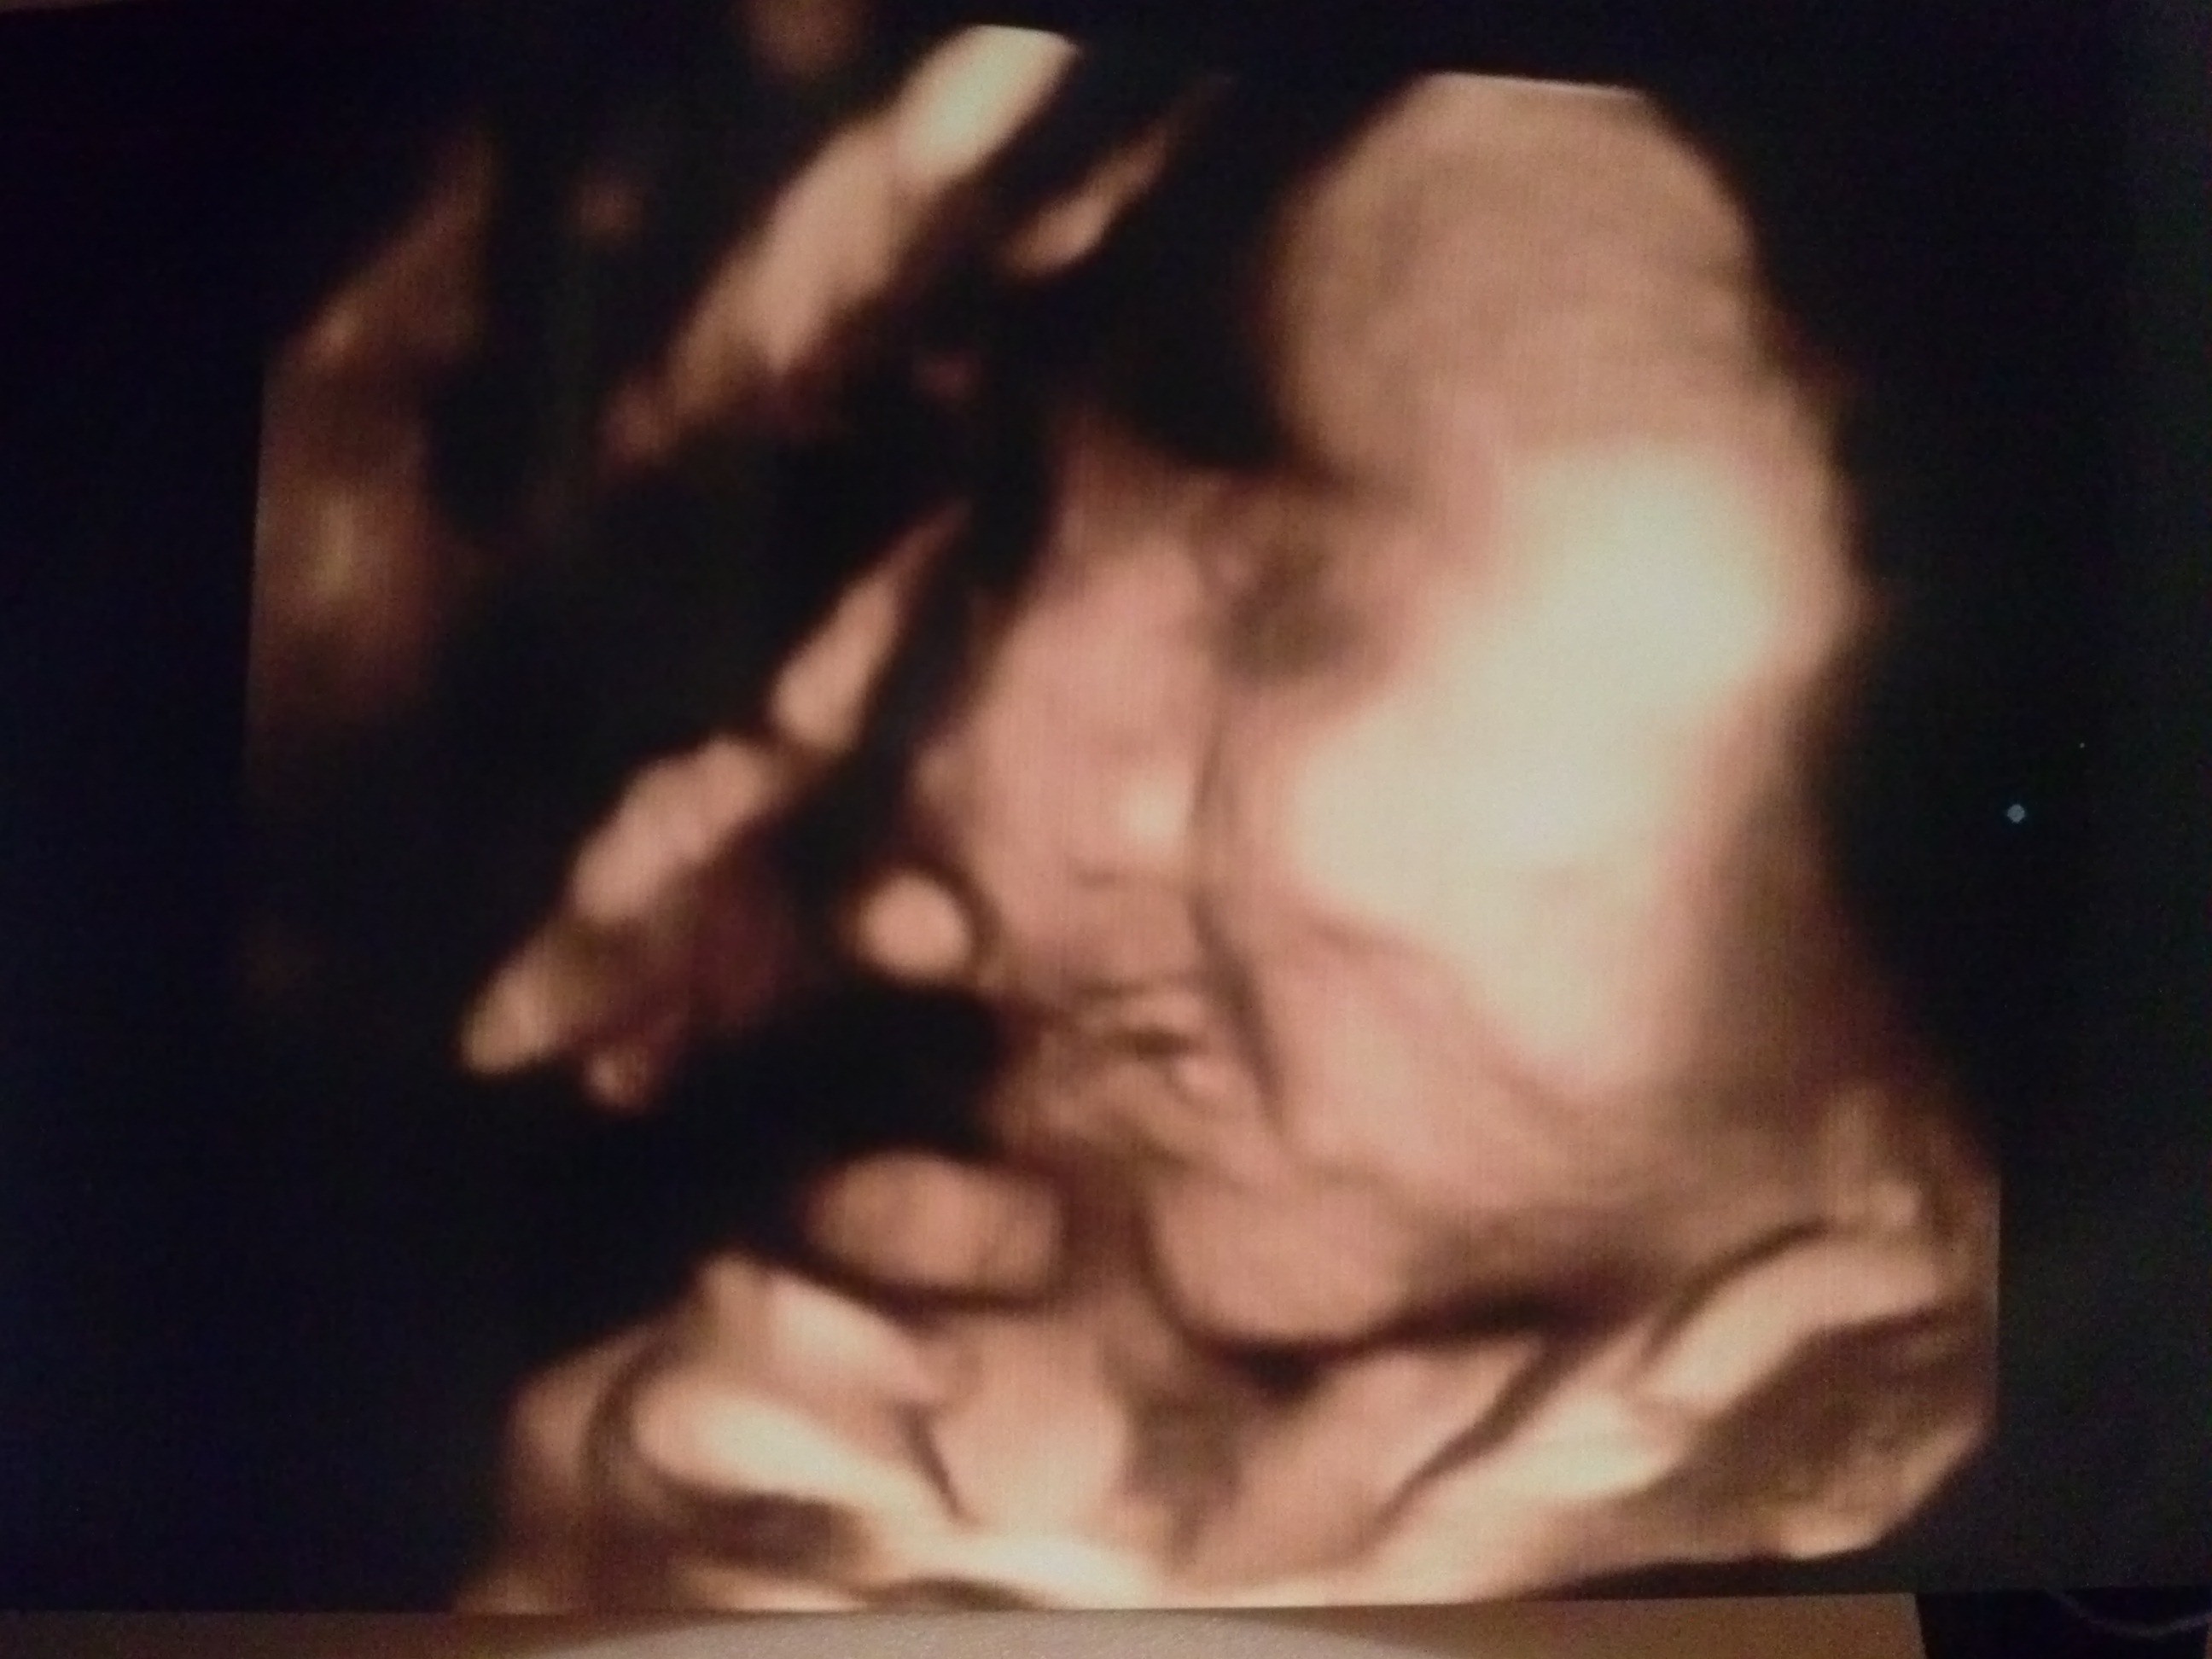

Byłam na usg. Mały jest zdrowy, ma ok. 1700g :) ułożony jest główką w dół. Szyjka długa i zamknięta 4,41cm, nawet kazał kaszleć jak trzymał głowicę usg nad szyjką, bo przy kaszlu podobno szyjka może się rozwierać. Na początku lekarz przyłożył głowicę do brzucha i dosłownie po 3 sekundach powiedział, że chłopiec ułożony główką w dół...zaskoczył mnie jak tak szybko to stwierdził;)no ale ma certyfikat z usg międzynarodowy i polski, więc doświadczenie ma:)Tylko mały cały czas zasłaniał twarz rączkami, więc zdjęcia 3d takie sobie. Zapytałam czy termin porodu się przesunął, to pokazał mi co przeliczył komputer i było 18.12.2019, ale powiedział, że ta data jest nieprecyzyjna i należy posługiwać się datą z pierwszego usg, czyli wychodzi 30-31 grudzień. Zapytałam też czy przed porodem powinnam zrobić znów usg (bo mi gin na wizytach nie robi usg), powiedział, że najlepiej zrobić w 36-37 tygodniu, aby sprawdzić wagę dziecka i poziom wód płodowych, bo jeśli będzie ich za mało to jest to niebezpieczne dla dziecka. Mam zdjęcia i płytę z filmikami z badania:)